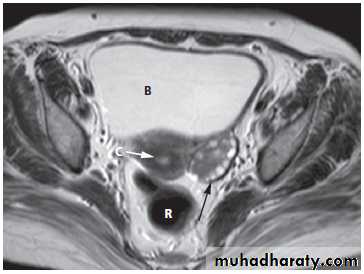

Magnetic resonance imagingPelvic anatomy is very well demonstrated because of the excellent soft tissue contrast afforded by MRI. Images are usually taken in the axial, coronal and sagittal planes . T2-weighted sagittal images show the vagina and cervix in continuity with the body of the uterus.

The zonal anatomy of the uterus is best demonstrated on T2-weighted images, with the endometrium having a high signal intensity, the adjacent inner myometrium (junctional zone) a low signal intensity, and the myometrium an intermediate signal intensity .

At CT fibroids are usually the same density as the adjacent myometrium. MRI can readily identify fibroids as they typically have a different signal characteristic from the normal uterus .

Adenomyosis is a benign condition in which there is endometrial tissue within the myometrium. This results in smooth muscle hypertrophy. Patients may present with dysmenorrhoea and abnormal uterine bleeding. The uterus is typically enlarged.On ultrasound, there is increased heterogeneity of the myometrium.

On MRI, there is focal or diffuse thickening of the junctional zone and, in some cases, multiple bright projections are seen extending from the endometrium into the myometrium .